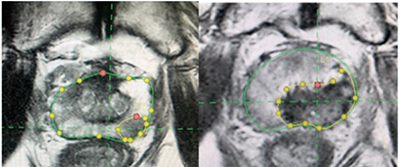

研究人员在该项Ⅱ期试验(PFLT-PC)中招募了100例前列腺特异性抗原(PSA)水平<15 ng/mL的、<T2c期的、国际泌尿病理学会(ISUP)分级分组为2~3的、多参数MRI有可见病灶的、局限性前列腺癌男性患者,在日间病房全身麻醉下给予ProFocal前列腺组织消融激光疗法的冷激光聚焦治疗(Medlogical Innovations)。

主要终点包括72小时内多参数MRI组织消融的充分性,以及治疗后3个月的活检情况。